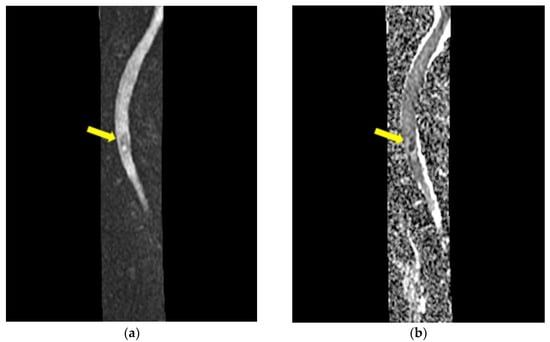

- Mycological demonstration of Aspergillus fumigates hyphae by microscopy from spu-tum, microscopy and culture from bronchial aspirate, and histopathological evi-dence of the presence of Aspergillus fumigates hyphae with dichotomous branching in the spinal cord biopsy;